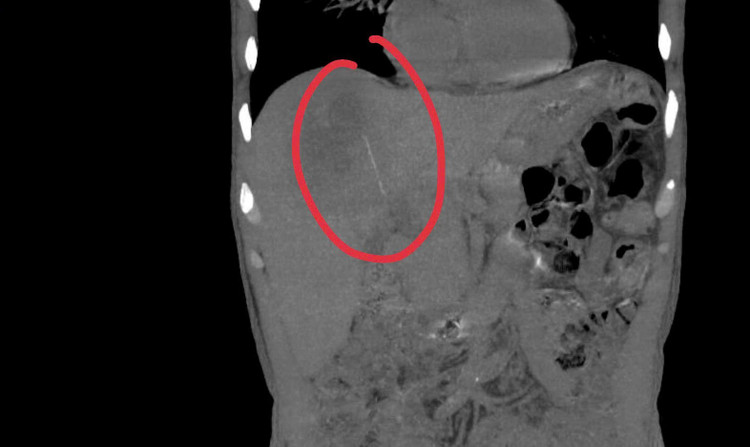

Hình ảnh dị vật tăm trong gan bệnh nhân - Ảnh BVCC

Bệnh nhân từng thăm khám và điều trị tại nhiều cơ sở y tế nhưng chưa xác định được nguyên nhân. Qua khám lâm sàng và tiến hành siêu âm bụng, các bác sĩ ghi nhận hình ảnh ổ áp xe gan, tuy nhiên, điểm bất thường là ổ áp xe nằm khá sâu, biểu hiện không điển hình. Vì vậy, bệnh nhân được chỉ định nhập viện để làm thêm các cận lâm sàng chuyên sâu.

Khi tiến hành siêu âm kỹ hơn, ê-kíp phát hiện một dị vật cản quang xuyên trong nhu mô gan, chiều dài ước tính khoảng 6-7cm. Ngay sau đó, bệnh nhân được chỉ định chụp cắt lớp vi tính (CT scan) ổ bụng.

Kết quả cho thấy có một dị vật dạng que dài nằm hoàn toàn trong nhu mô gan, kèm theo ổ áp xe sâu. Trước nguy cơ biến chứng nặng nếu không điều trị kịp thời, ê-kíp khoa Nội tiêu hóa đã nhanh chóng hội chẩn cùng khoa Ngoại Gan Mật Tụy, thống nhất phương án phẫu thuật lấy dị vật, dẫn lưu ổ áp xe, kết hợp điều trị kháng sinh phù hợp.